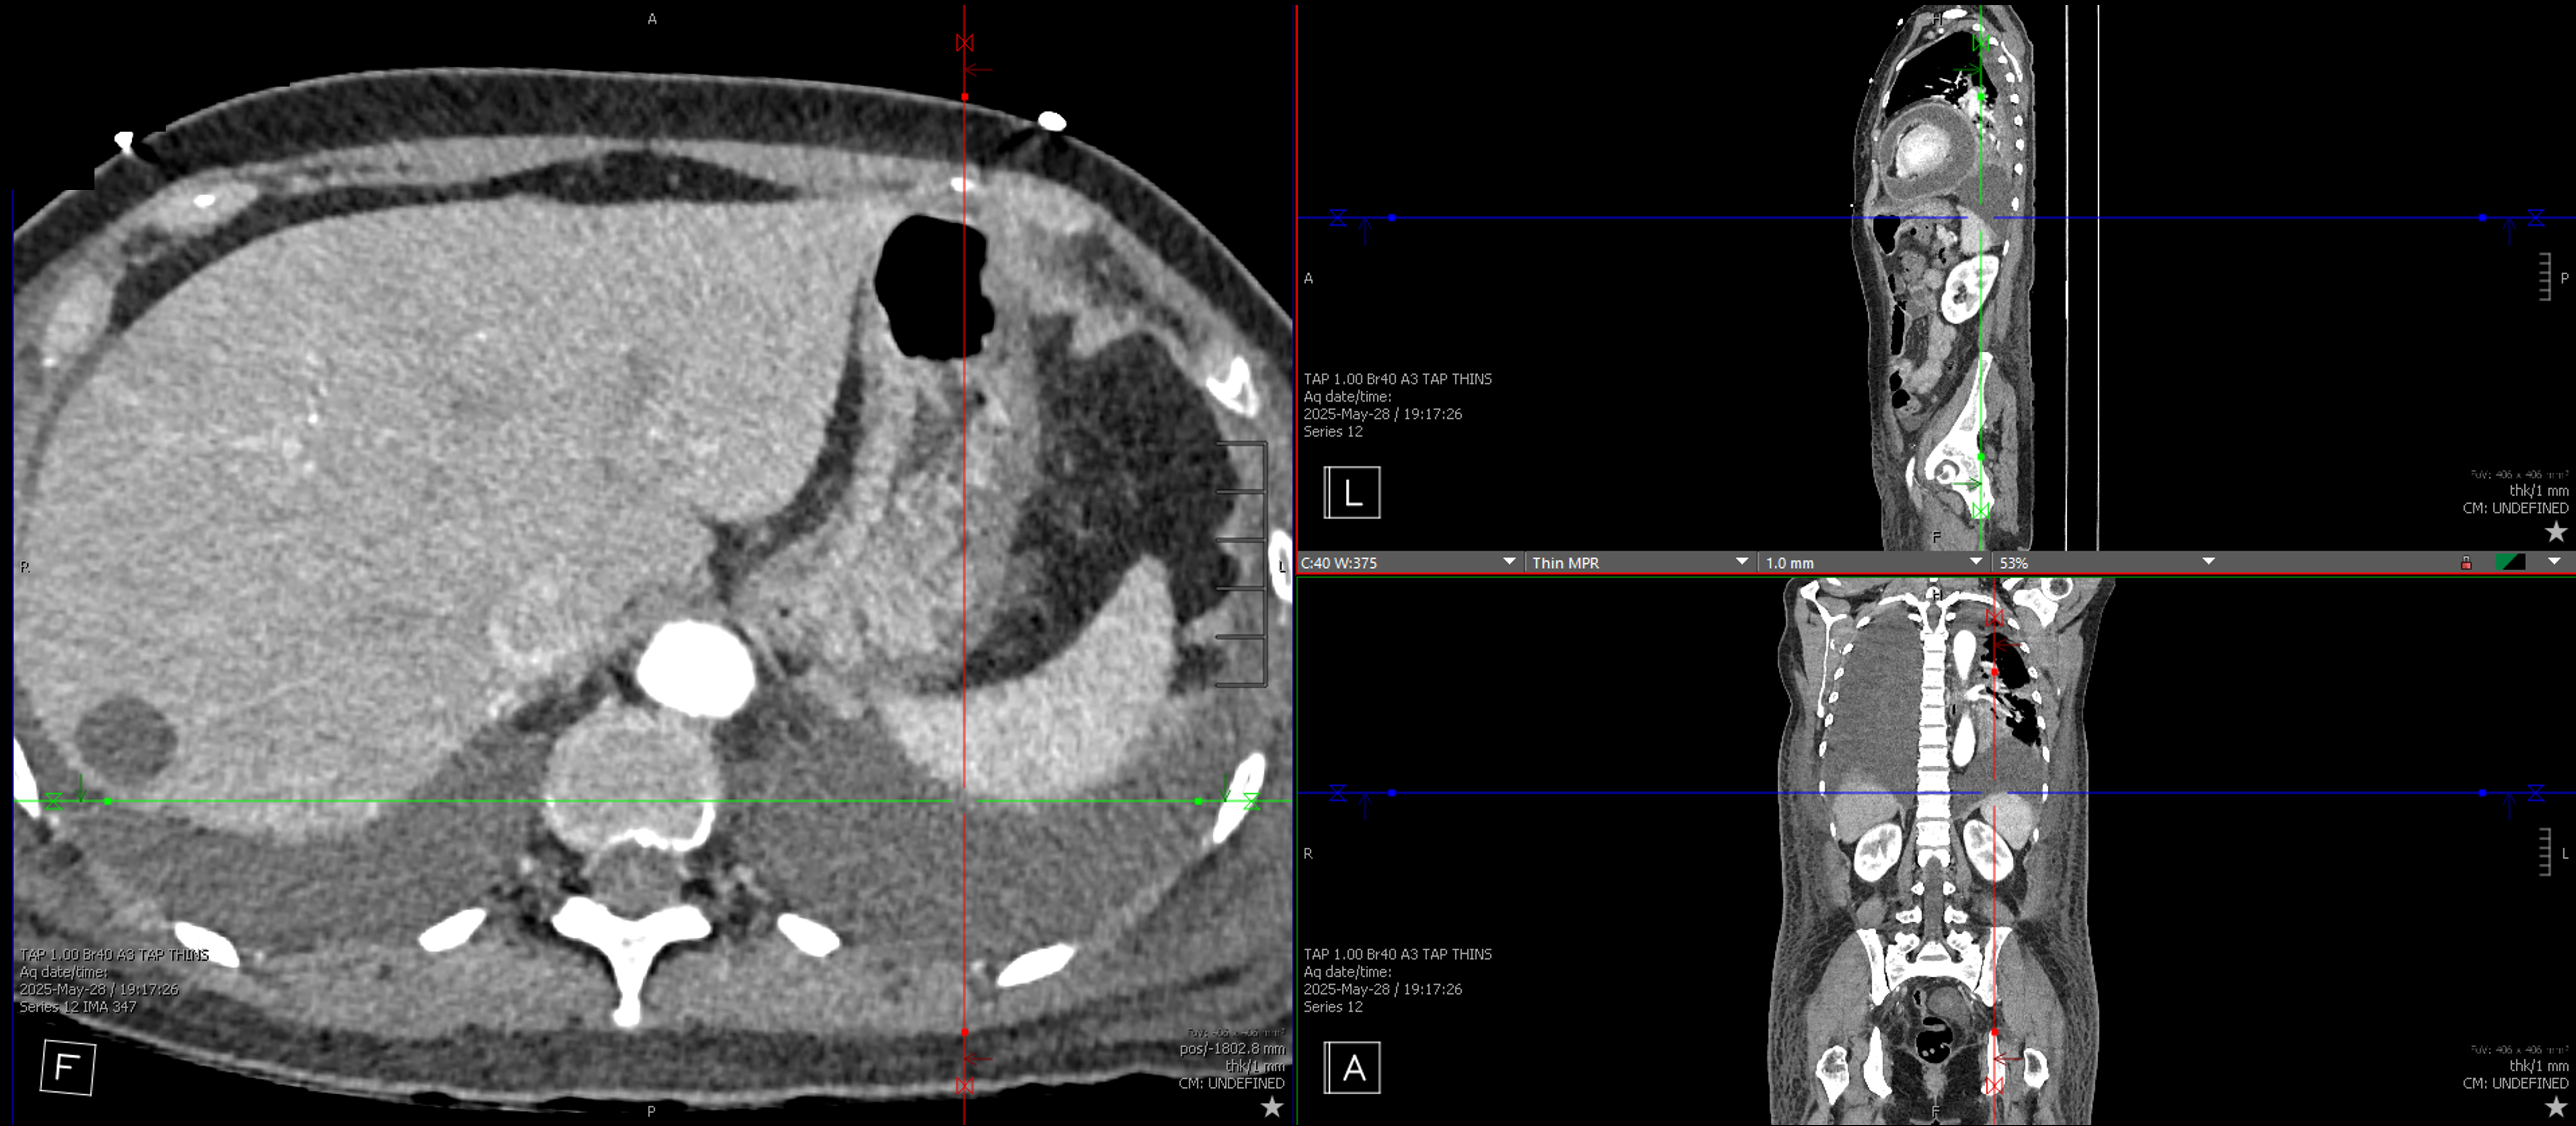

A 55-year-old previously healthy woman presented to hospital with abdominal pain, fever, and dyspnea. She was hypotensive (SBP 70mmHg), acidotic (lactate >16 mmol/L), and leukocytotic (WBC 26.3 × 109/L). Imaging revealed a large pericardial effusion with tamponade physiology and a 6×7×3.5 cm hepatic abscess. Pericardiocentesis yielded 600 mL of purulent fluid, and hepatic abscess drainage followed. Cultures from both sites grew Hypervirulent Klebsiella pneumoniae (hvKp). Despite initial improvement, she experienced recurrent fevers and dyspnea, prompting transfer to our facility. Repeat CT imaging demonstrated rapid re-accumulation of a loculated pericardial effusion with echocardiography suggesting effusive-constrictive physiology. Ultimately patient required a pericardial window. Exploration of the pericardial space demonstrated a connection along the inferior aspect of the pericardium traversing the diaphragm and into the peritoneum at which site the liver was noted to be attached. The liver was bluntly resected off the diaphragm and a large communication between the two cavities was identified. A piece of omentum was placed between the liver and the diaphragm which acted as an omental patch. She made a full recovery thereafter.